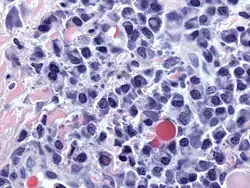

![]() Micrograph of malignant plasma cells (plasmacytoma), many displaying characteristic "clockface nuclei", also seen in normal plasma cells. H&E stain. | |

Plasma cells are large lymphocytes with abundant cytoplasm and a characteristic appearance on light microscopy. They have basophilic cytoplasm and an eccentric nucleus with heterochromatin in a characteristic cartwheel or clock face arrangement. Their cytoplasm also contains a pale zone that on electron microscopy contains an extensive Golgi apparatus and centrioles. Abundant rough endoplasmic reticulum combined with a well-developed Golgi apparatus makes plasma cells well-suited for secreting immunoglobulins.[4] Other organelles in a plasma cell include ribosomes, lysosomes, mitochondria, and the plasma membrane.

Plasmacytoma, multiple myeloma, Waldenström macroglobulinemia, heavy chain disease, and plasma cell leukemia are cancers of the plasma cells.[33] Multiple myeloma is frequently identified because malignant plasma cells continue producing an antibody, which can be detected as a paraprotein. Monoclonal gammopathy of undetermined significance (MGUS) is a plasma cell dyscrasia characterized by the secretion of a myeloma protein into the blood and may lead to multiple myeloma.[34]